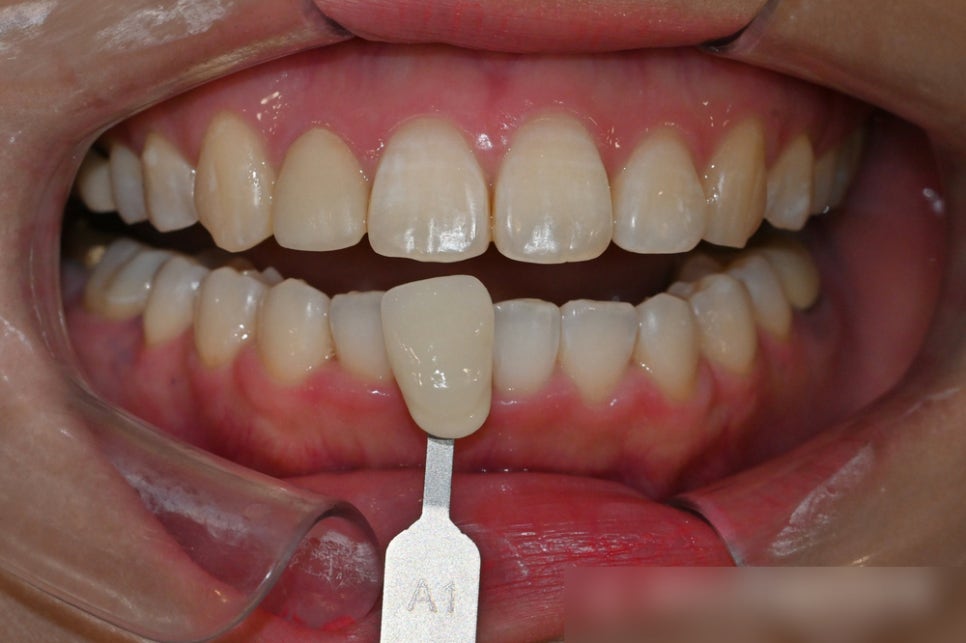

진료가 끝나고! 누런 치아를 하얗게

바꾸고 싶다는 말씀을 하셨기에

중화동 치과 치아미백까지

한 곳에서 도와드릴 수 있었습니다.

이렇게 놓고 보니 정말 다른사람 같지 않나요?

다행히 임플란트도 재수술을 진행 할 필요가 없었고

전치부 돌출감 없이 진료를 잘 마칠 수 있었죠.

치료기간 : 23.10.20 ~ 24.10.23